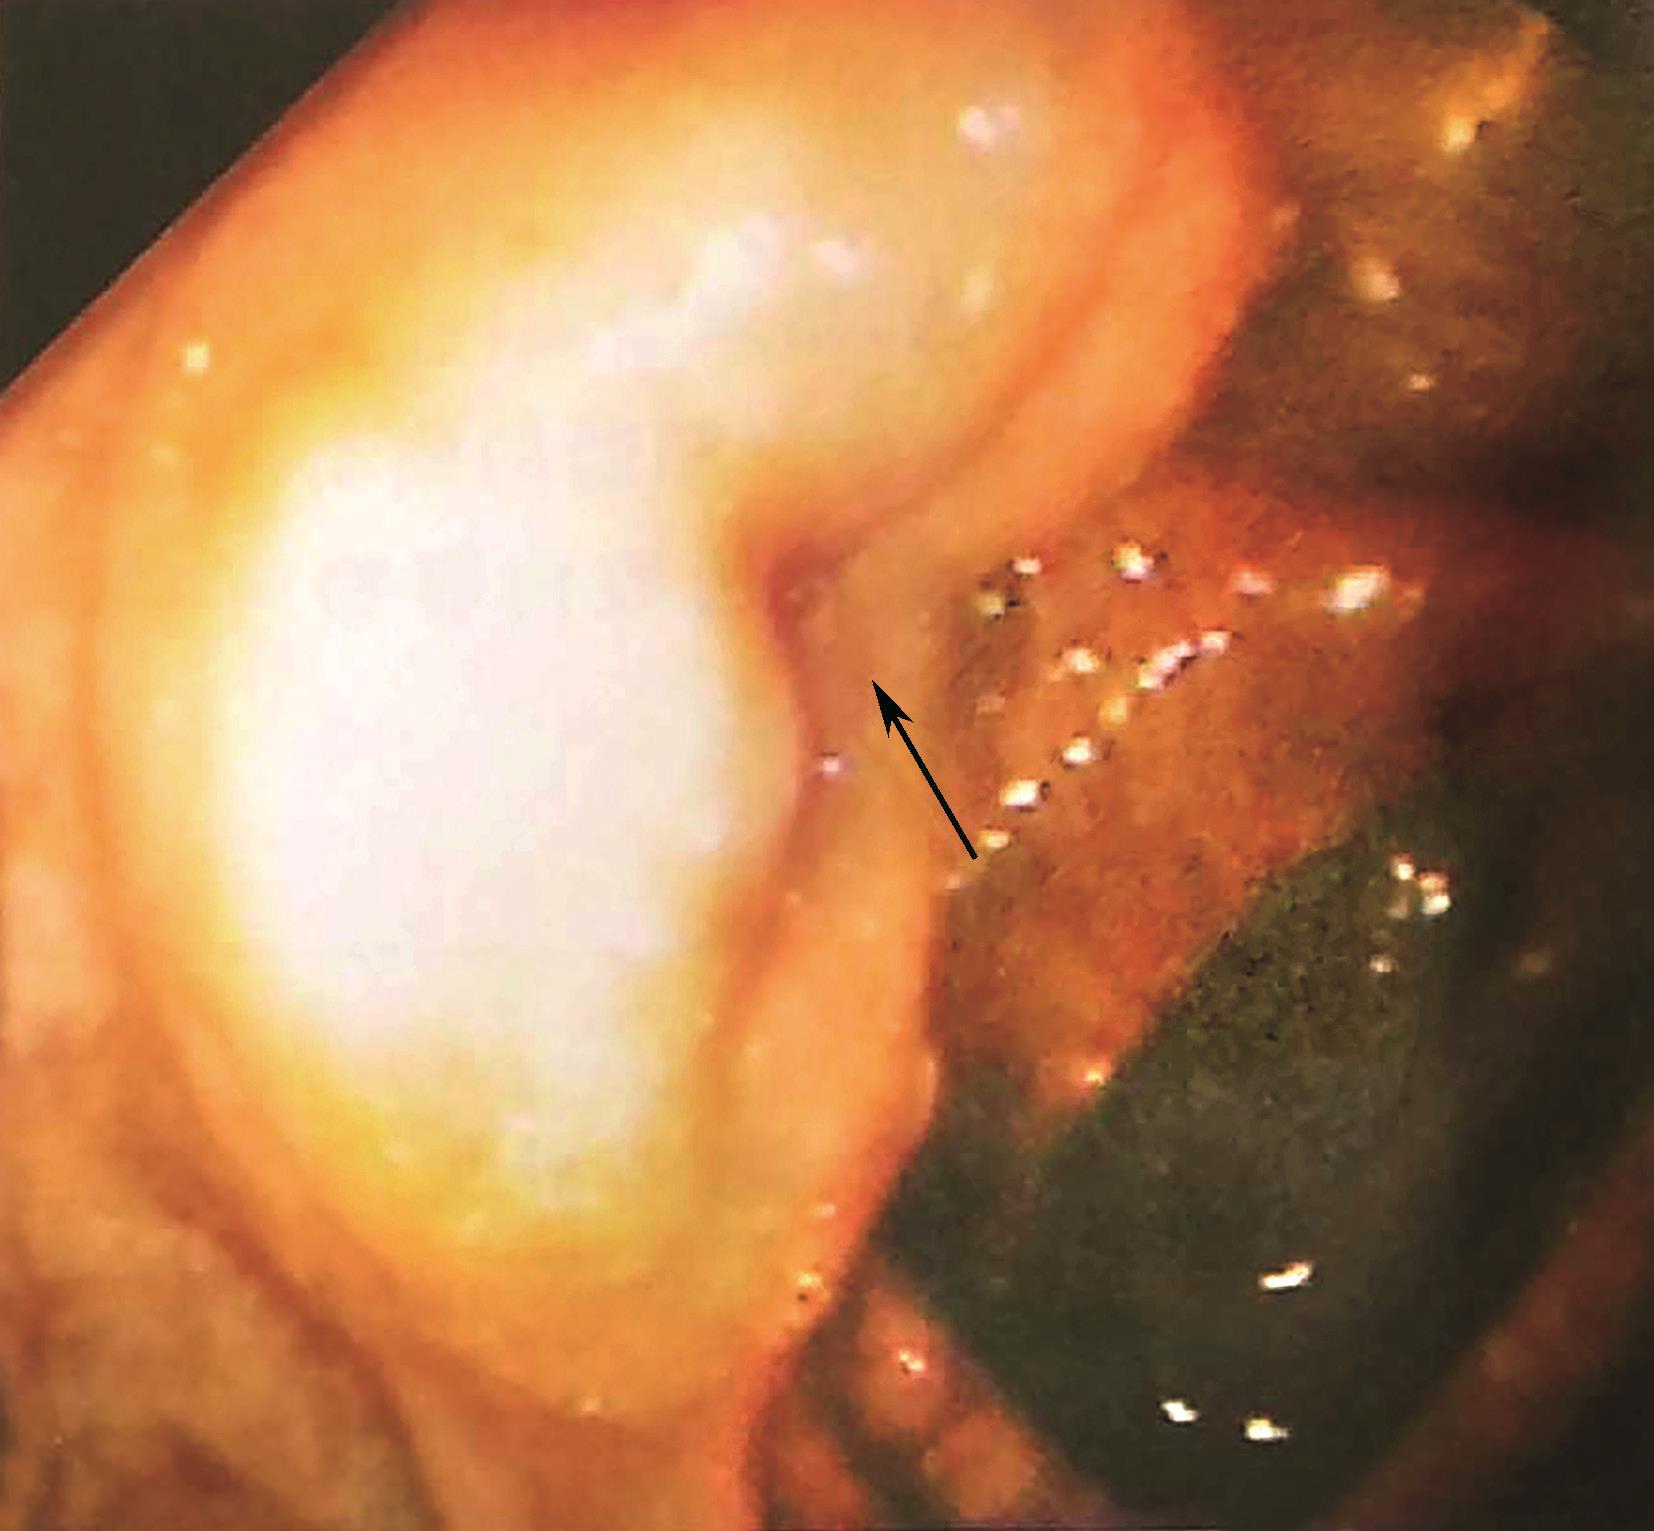

盲肠为腹膜内位器官,移动性较好,没有系膜结构,腹膜折叠常将盲肠附着在髂窝外侧和内侧。这些褶皱形成一个小的陷凹,称为结肠后窝(图2-1)。回肠和盲肠的韧带维持末端回肠和盲肠之间的夹角,形成了回肠末端突入盲肠的类似上下唇样的结构,称回盲瓣(图2-2)。这些结构在调节小肠内容物进入结肠的速度和预防回肠末端的食糜回流发挥重要作用[结肠内压可达80mmHg(1mmHg=0.133kPa)]。因此,临床上不要轻易切除回盲部;在短肠综合征的病例中,是否具有回盲瓣,对该病的诊断和预后均有重要意义。

图2-2 回盲瓣(结肠镜下观)

箭头示回盲瓣。